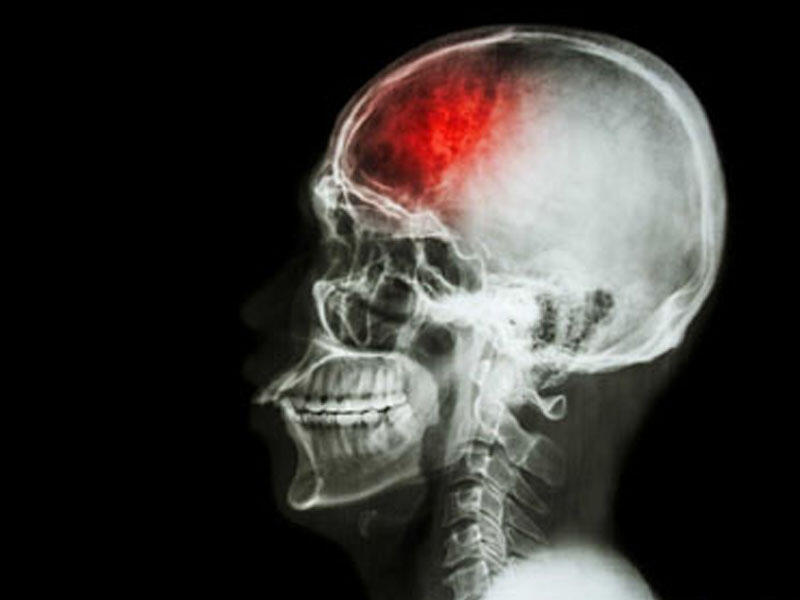

Kəllə beyin travmasının nəticələri

Beyin travması keçirmiş adamlarda bir-neçə ay ərzində diffuz baş ağrıları baş verə bilir.Bu ağrılar bəzən səhərlər baş versə də,çox vaxt gün ərzində gərginlik,narahatlıq törədir.Beyin travması almış xəstələrdə baş ağrıları aşağıdakı hallarda meydana çıxa bilir:

Beyin travması almış xəstələrdə bəzən zədə nahiyəsində lokallaşmış baş ağrıları meydana çıxır.Zədələnmə xəstələrdə ən çox baş gicəllənməsi,baş hərlənməsi,yeriş zamanı səndələmək,cəld hərəkətlər və yerdən qalxan zaman qətiyyətsizlik müşahidə olunur.Belə xəstələrdə bəzi beyin əlamətləri meydana çıxır:

Ağır kəllə beyin travması zamanı kəllə sinirlərinin zədələnməsi,hemiparez şəklində beyin pozulmaları müşahidə edilə bilir.Bəzən xəstələrdə hissiyyat və nitq pozulmalarına təsadüf edilir.